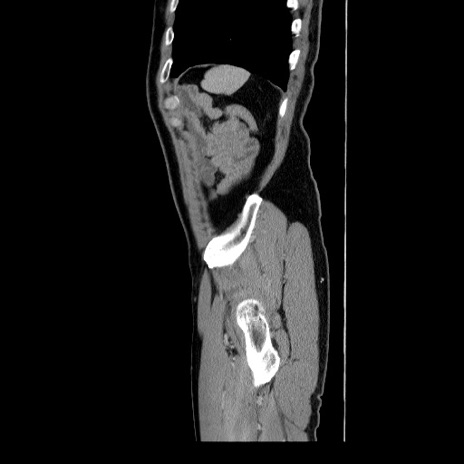

症例34(矢状断像)

【症例】60歳代 男性

【主訴】右鼠径部膨隆

【現病歴】1年程前より右鼠径部膨隆あり。自己にて還納可能だったため放置していた。3時間前より右鼠径部の脱出を認め、還納困難となり受診。

【既往歴】高血圧

【身体所見】右鼠径部に小児頭大の膨隆あり。弾性硬であり、用手還納は困難。左鼠径部にも膨隆を認める。脱出はなし。